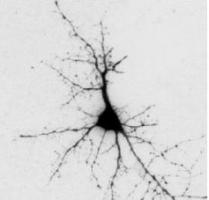

PARKINSON : Reprogrammer des cellules productrices de dopamine, c'est possible

PARKINSON: On sait produire des neurones dopaminergiques de qualité